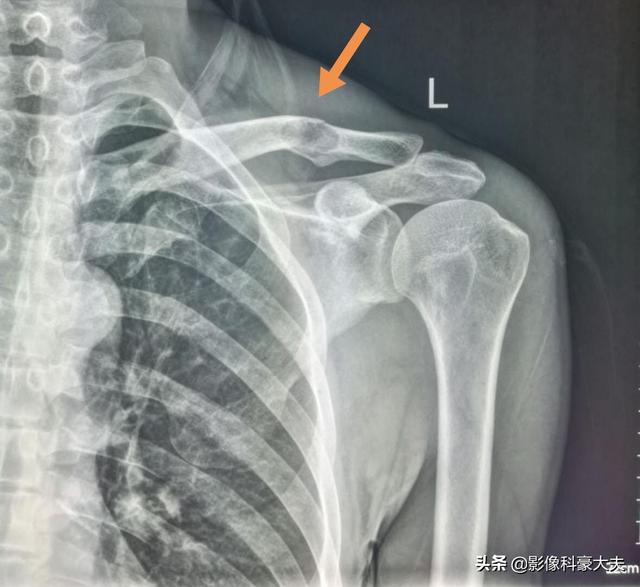

5年間生存している低分化癌の鎖骨転移

この症例は58歳のゲイ男性で、肩を軽く伸ばしただけで痛みが続くようになり、X線検査で低密度病巣が見つかった:

これは骨転移に基づく軽微な外力による病的骨折であった。穿刺が行われ、病理結果は低分化肺腺癌の骨転移であった。

左肺にあるこの不規則な結節が原発巣で、わずか2.6cmしかない。このような骨転移を伴う肺がんは、もはや手術不可能です。肺がんはあまりにもありふれた病気であり、初期症状の中には非典型的なものや無症状のものさえあるからだ。肺がんの約30%では、転移の症状が最初の症状であり、さらなる肺がんが発見される前に転移が最初に発見される。